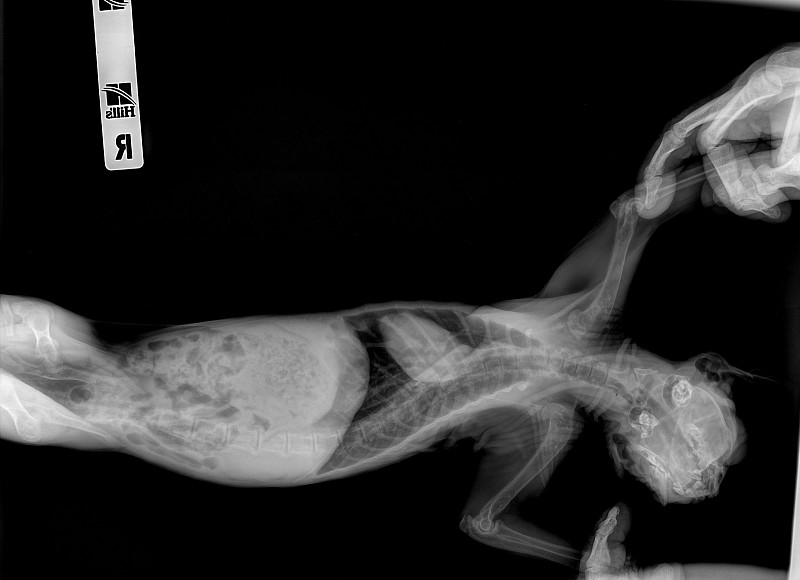

Здравствуйте, у нас сфинкс, девочка 7 мес, стерилизована. питается натуральной пищей+ витамины. Около месяца назад начали замечать малоподвижность, хождение маленькими шажками, с трудом забирается на свои любимые места. Травм не было. Тазовые конечности поджимает под себя. Мы сдали кровь:Мочевина завышена-16.6, щелочная фосфатаза - 558, кальций 1.76, фосфор 2.07. Сказали скорей всего вторичный гиперпаратиреоз. Сделали рентген, снимки прикреплю. В снимках написали еще лордоз в поясничном-крестцовом отделе. Что это?Лечится ли, могло ли это быть тоже последтвием вторичного гиперпаратиреоза?

Добрый день. Да, действительно по рентген снимкам у вас подозрение на алиментарный гиперпаратиреоз. Лордоз является последствием гиперпаратиреоза. Вам рекомендовано перейти на промышленный корм премиум класса, ограничить физические нагрузки, а именно прыжки с высоты. При боли можете принимать обезболивающие препараты типа Неболин вет/Мелоксивет по 0.05 мг/кг 1 р/д после кормления. Касаемое различных витаминов и кальция, тут вопрос спорный, их прием необязательный. На данном этапе с лордозом делать ничего не надо. В будущей если вдруг проявятся признаки неврологического дефицита (шаткость походки, малоподвижность) сделайте магнито-резонансную томографию (МРТ) грудно-поясничного отдела позвоночника. После описанных рекомендаций переделайте рентген снимки через 3 мес.